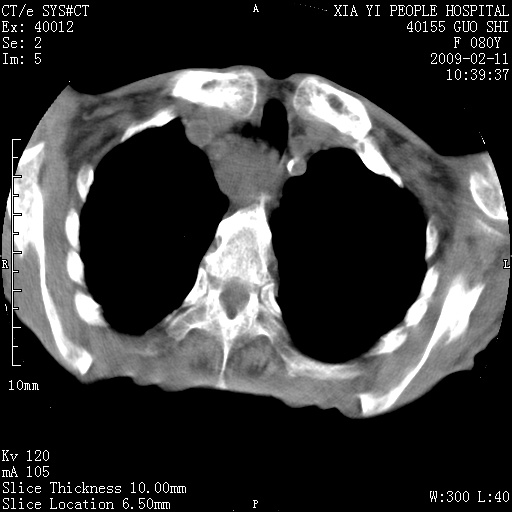

以下是引用随光逐影在2009-2-16 16:34:00的发言:[br]1)考虑右前纵隔皮样囊肿。2)双侧少量胸腔积液。

以下是引用zjzjr在2009-2-16 17:30:00的发言:[br]支持囊性畸胎瘤 双侧少量胸腔积液。